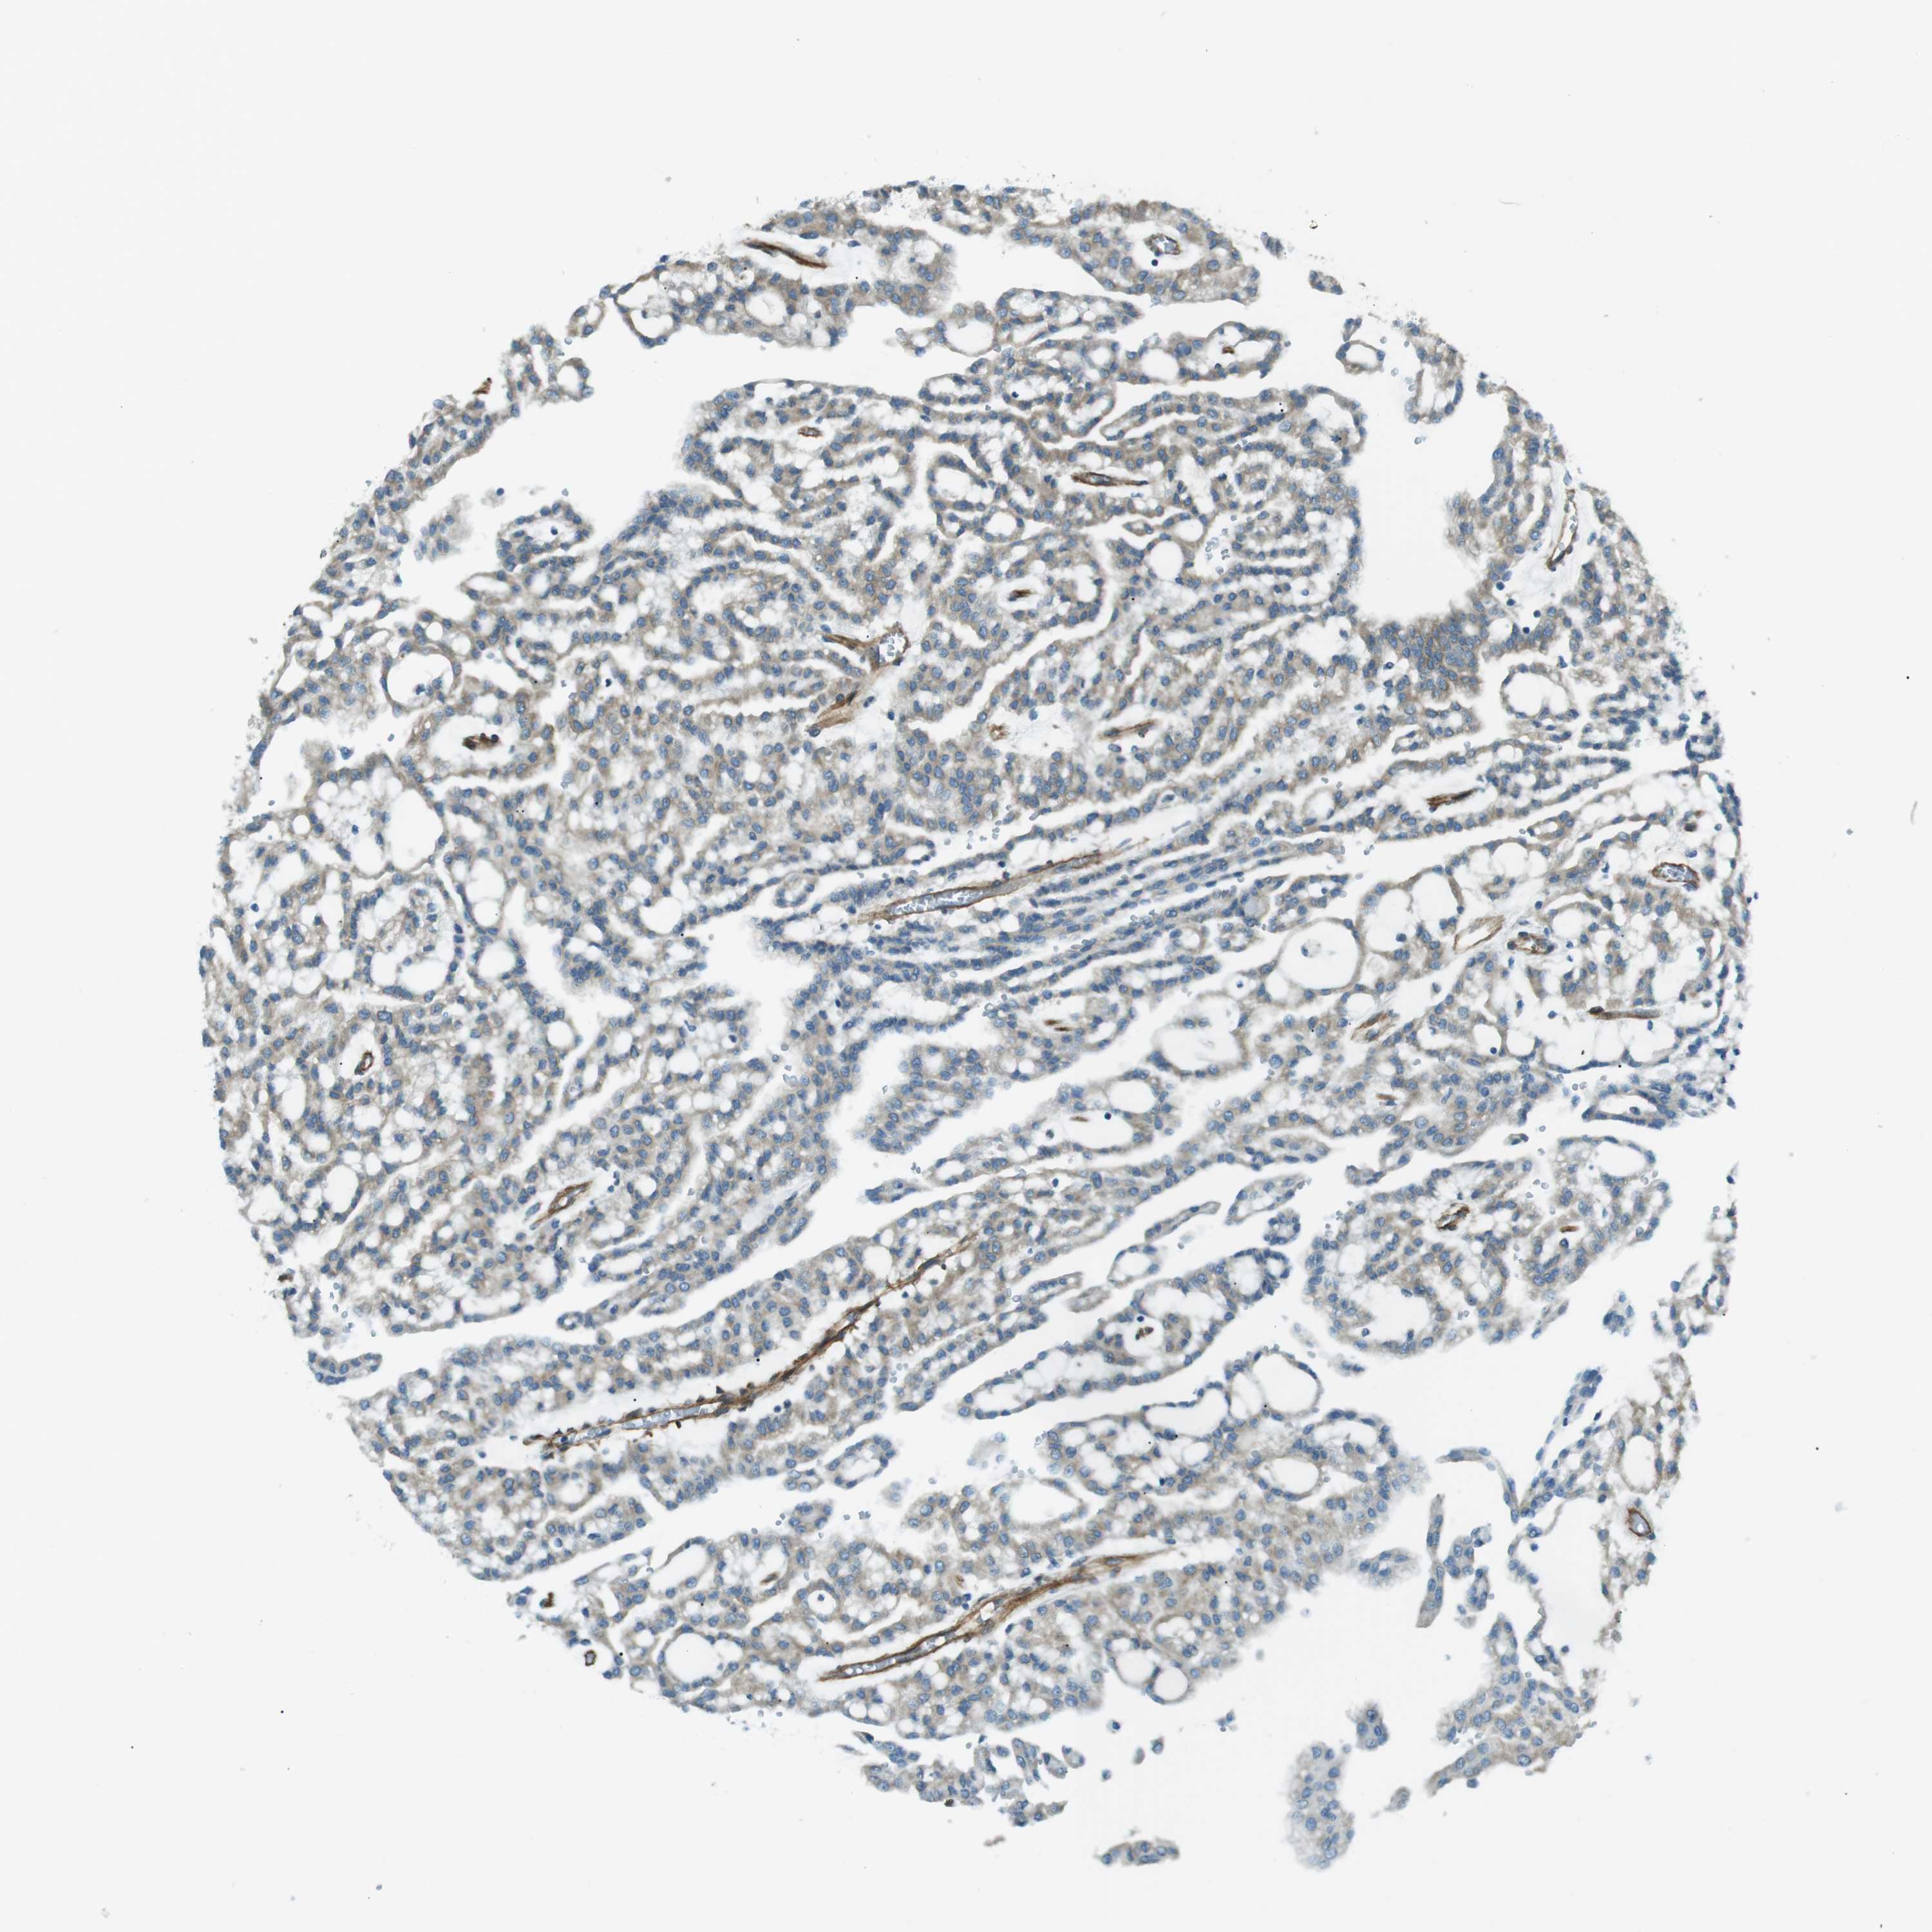

KIDNEY RENAL PAPILLARY CELL CARCINOMA (TCGA) - Interactive survival scatter ploti

The Survival Scatter plot shows the clinical status (i.e. dead or alive) for all individuals in the patient cohort, based on the same data that underlies the corresponding Kaplan-Meier plots. Patients that are alive at last time for follow-up are shown in blue and patients who have died during the study are shown in red.

The x-axis shows the expression levels (FPKM) of the investigated gene in the tumor tissue at the time of diagnosis. The y-axis shows the follow-up time after diagnosis (years). Both axes are complimented with kernel density curves demonstrating the data density over the axes. The top density plot shows the expression levels (FPKM) distribution among dead (red) and alive patients (blue). The right density plot shows the data density of the survived years of dead patients with high and low expression levels respectively, stratified using the cutoff indicated by the vertical dashed line through the Survival Scatter plot. This cutoff is automatically defined based on the FPKM cutoff that minimizes the p-score. The cutoff can be changed by dragging the vertical line or by entering a cutoff value in the square labeled "Current cut-off".

Under the Survival Scatter plot the p-score landscape (black curve; left axis) is shown together with dead median separation (red curve; right axis). Dead median separation is the difference in median mRNA expression between patients who have died with high and low expression, respectively. It is calculated as follows: median FPKM expression of dead patients with high expression - median FPKM expression of dead patients with low expression. This is intended to aid the user in visually exploring custom cutoffs and the associated p-scores and dead median separation.

Individual patient data is displayed and can be filtered by clicking on one or more of the category buttons on the top of the page. Categories describing expression level and patient information include: high, low, alive, dead, female, male and tumor stages. The scale of the x-axis can be toggled between linear and log-scale by clicking on the "x log" button. Mouse-over function shows TCGA ID, patient information and mRNA expression (FPKM) for each patient.

& Survival analysisi

Kaplan-Meier plots summarize results from analysis of correlation between mRNA expression level and patient survival. Patients were divided based on level of expression into one of the two groups "low" (under cut off) or "high" (over cut off). X-axis shows time for survival (years) and y-axis shows the probability of survival, where 1.0 corresponds to 100 percent.

ODR4 is not prognostic in Kidney Renal Papillary Cell Carcinoma (TCGA)

Best expression cut offi

Based on the FPKM value of each gene, patients were classified into two groups and association between prognosis (survival) and gene expression (FPKM) was examined. The best expression cut-off refers the FPKM value that yields maximal difference with regard to survival between the two groups at the lowest log-rank P-value. Best expression cut-off was selected based on survival analysis .

When clicking on this number, the vertical dashed line indicating cut-off, the interactive survival plot, and the Kaplan-Meier curve will be adjusted to show results based on the best expression cut-off.

: 13.4